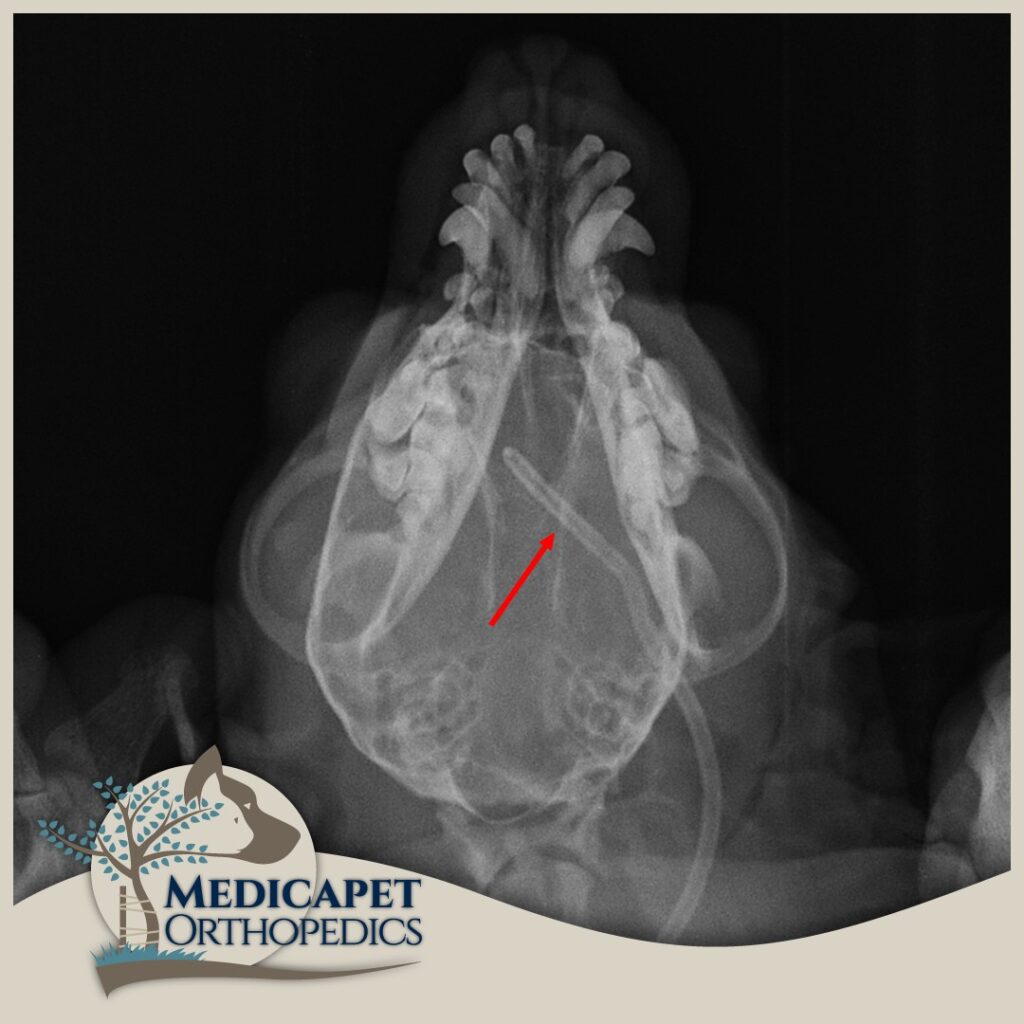

CERRAHİ TEDAVİ Ventriculoperitoneal Şant uygulamasını kapsar. Ventriküllerde üretilerek sistemik dolaşıma katılamayan ve beyine yüksek derecede basınç uygulayan BOS’un beyinden kalbe ya da karın boşluğuna aktarılmasını sağlayan bir sistemin yerleştirilmesi işlemidir. Yüksek seviyede tecrübe gerektiren bir operasyondur. Beynin içerisine yerleştirilen bir kateter ense kısmında deri altına yerleştirilmiş olan bir vanaya bağlanır. Bu otomatik slikon vana beyin içerisindeki basınç artınca açılarak kendisine bağlı olan diğer katetere fazla BOS sıvısını akıtarak karın boşluğuna ya da kalbe iletilmesini sağlar. Bu bölgelere gönderilen fazla BOS buralardan emilerek sistemik dolaşıma geçer ve vücut dışına atılır. Medicapet rutin olarak bu ameliyatı yapan Türkiye’deki bir kaç merkezden biridir. Hidrosefalinin cerrahi tedavisinde başarı oranımız oldukça yüksektir. Operasyon sonrasındaki iyileşme oranı, hastanın beyin dokusunun almış olduğu hasarın boyutuna ve ne kadarının reversbl olduğuna bağlıdır. erken müdahale edilen hastanın yaşamsal fonksiyonlarının ve yüksek yaşam standardının korunması daha olasıdır.